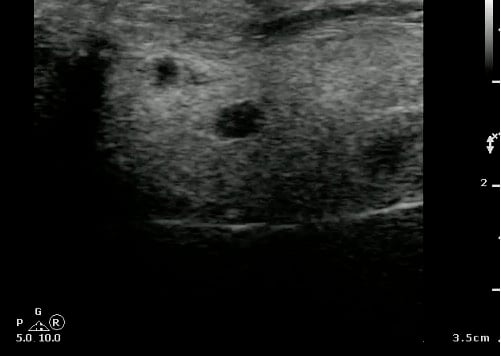

- Probe selection:

- A 5.0 to 10.0 MHz curved array intracavitary probe is used to evaluate a suspected PTA for intraoral ultrasound. Alternatively, a high frequency linear array transducer can be used for transcervical approach, especially in children or patients with severe trismus.